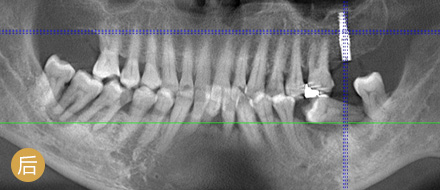

数字化精确导航种植

导航辅助种牙,创口小更舒服

• >智能导航,精确高效

• >适用症广,缺牙重生

• >避免盲种,成功率高

• >种牙精准,不伤神经